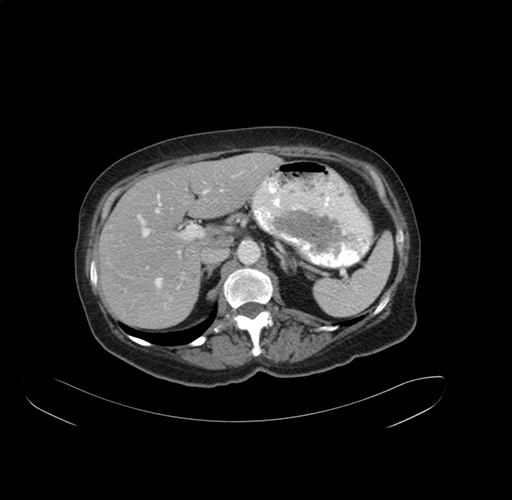

Pre-Chemo: Axial Venous

Axial Venous